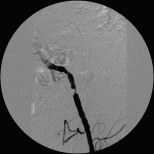

Abb.: Hochgradige Einengung in der Beckenarterie links, durch Ballonkatheter erfolgreich aufgeweitet

Gefäßrisikofaktoren wie Nikotin, erhöhter Blutdruck, Diabetes und Cholesterin können zu Engstellen und

Verschlüssen an den Arterien von Armen und Beinen führen. Diese machen sich dann durch Schmerzen in der Muskulatur bei körperlicher Anstrengung besonders beim Laufen bemerkbar. Man spricht dann von

„Schaufensterkrankheit“. Die Heilung von Wunden ist dann behindert. In schweren Fällen kann die Extremität gefährdet sein.

Schon vor 30 Jahren wurde ein Verfahren entwickelt, Engstellen in den Arterien mit einem Ballonkatheter

aufzuweiten. Der technische Fortschritt hat dazu geführt, dass immer kompliziertere Einengungen der Arterien mit

dem Ballonkatheter unter örtlicher Betäubung behandelt werden können. Zum Teil ist es dann nötig Gefäßstützen, sog. Stents, in das Gefäß einzusetzen.